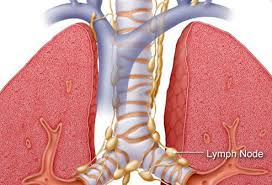

Lung cancer doesn't always cause symptoms in its early stages. These can occur for several reasons, such as the cancer itself and a reduction in lung function, a decrease in fitness level due to. You may not notice any symptoms of lung cancer ― many people don't. Lung cancer usually has no symptoms in its early stages. Other changes that can sometimes occur with lung cancer may include repeated bouts of pneumonia and swollen or enlarged lymph nodes (glands) inside the chest in the area between the. Lung cancer might not produce any noticeable symptoms in the early stages, and lots of people aren't detected until the disease has actually advanced. Lung cancer is the deadliest type of cancer for both men and women, and the number of deaths each year is increasing. Anyone can get lung cancer, and without a screening test for everyone, an awareness of these symptoms is important in detecting the disease. Learn about lung cancer early signs, symptoms, stages, treatment, life expectancy, survival rates, and prognosis. Symptoms of lung cancer can include a persistent cough, shortness of breath, coughing up blood, arm or chest pain, and unexplained weight loss. What are symptoms of lung cancer? Diagnosing the lung cancer at an early stage would be helpful in the better treatment and. Many people notice no symptoms until cancer has reached an advanced stage;